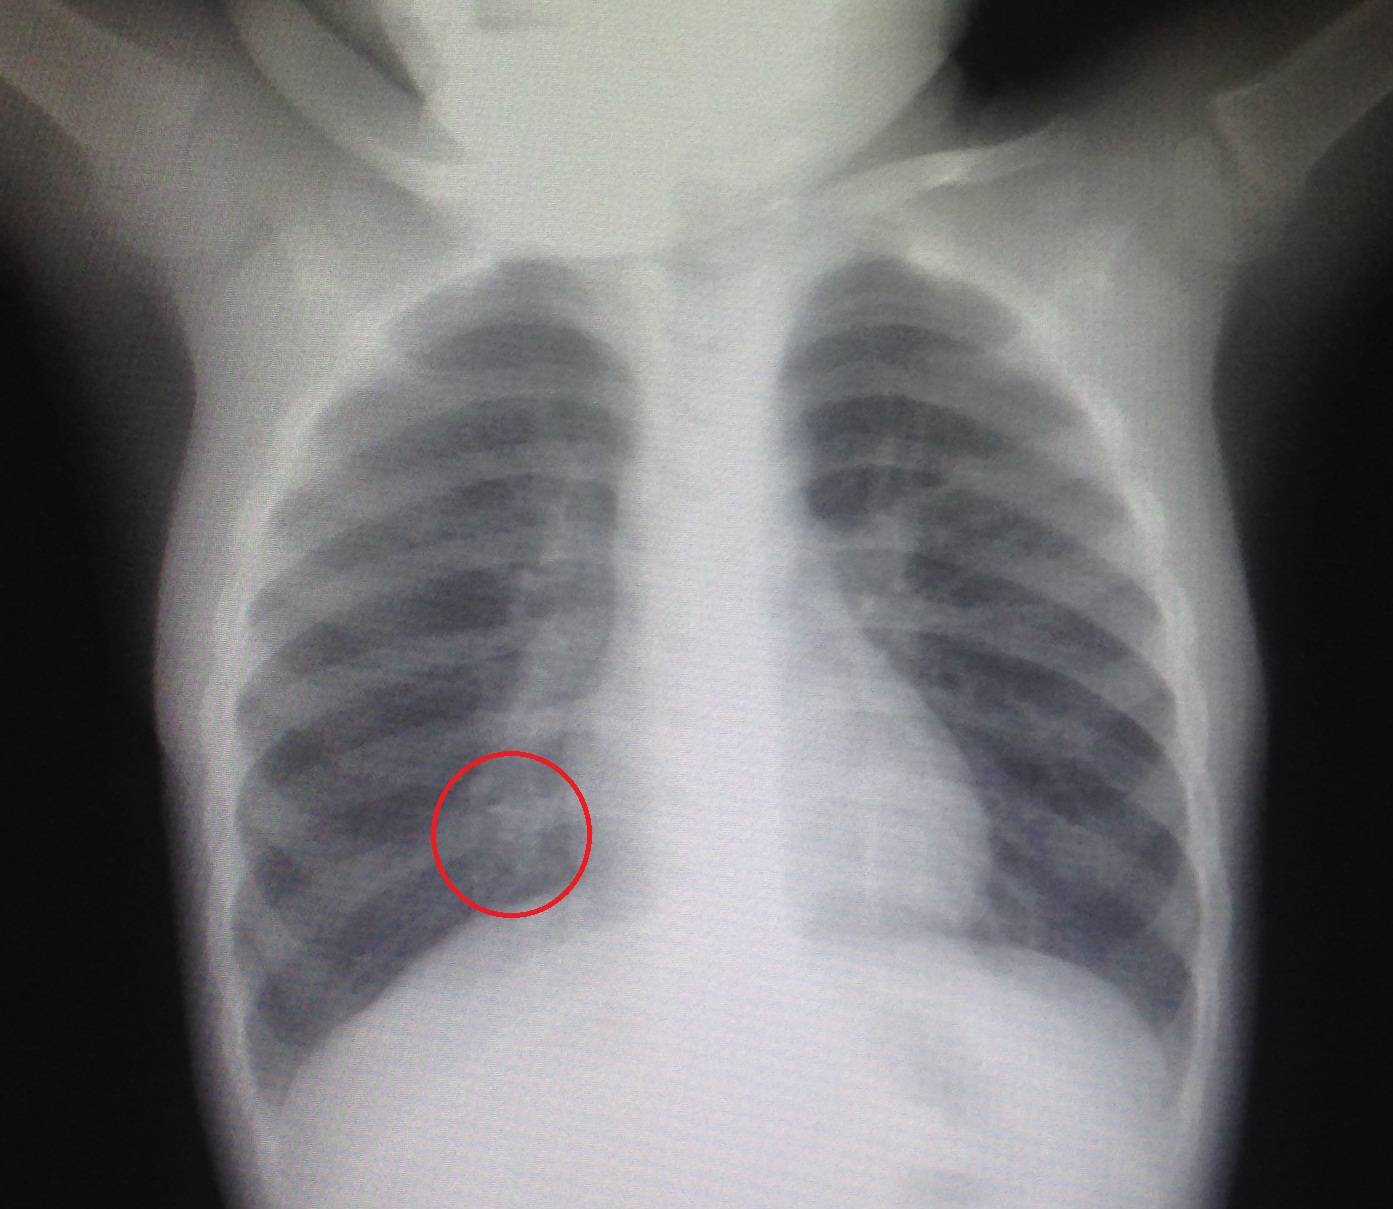

Рентгенография легких

Как видно из таблицы, и лабораторные исследования не дают спорные результаты, поэтому для установки окончательного диагноза используют рентгенографию легких. Рентгеновский снимок легких показывает признаки пневмонии у грудничков и старших детей — участки инфильтрации легочной ткани и их размер.

На фото участок легкого пораженный воспалительным процессом

Исходя из области поражения легкого, врач определяет тип пневмонии:

- долевая – поражена доля легкого;

- сегментарная – сегмент легкого;

- полисегментарная – несколько сегментов;

- очаговая – группы альвеол;

- бронхопневмония – затронута часть легочной ткани и бронхи;

- интерстициальная – интерстициальная ткань.